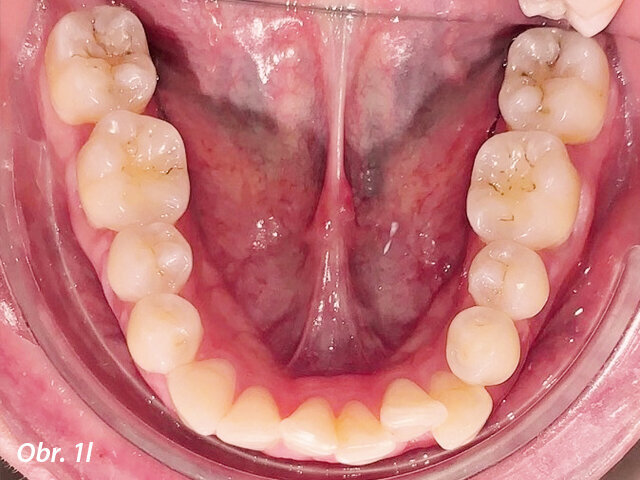

Pacientka 1 – Počáteční fotografie.